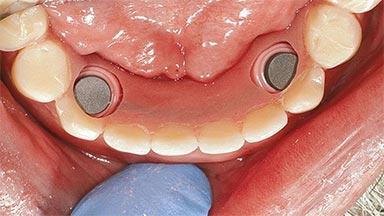

Type of Implants One-Piece

Attachment One-Piece